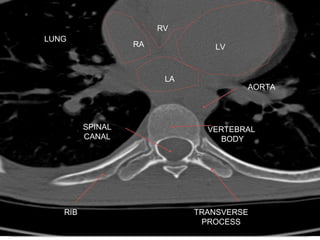

Computed Tomography (CT)

1. Also called CAT scanning or “CT”

2. X-Ray beam moves 360 around the patient

3. Consecutive x-ray “slices” around the patient

4. Computer can recreate 3D image of the body or

Image “slices” reconstructed by computation

5. Best for evaluating bone and soft tissue tumors,

fractures, intra-articular abnormalities, and

bone mineral analysis

Computed Tomography

6. The image formed is related to the subjects

density

7. Image display on computer or multiple films

8. New technology is multislice helical scanner

CT (by Picker)

LV

VERTEBRAL

BODY

SPINAL

CANAL

TRANSVERSE

PROCESS

RIB

LUNG

RA

LA

RV

AORTA